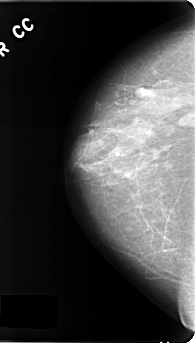

C_0177_1.RIGHT_CC